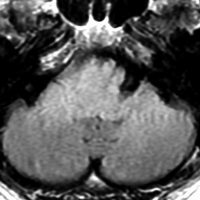

MRI画像所見 60代で嚥下障害と構音障害で発症した例

延髄から中脳まで腫瘍があって脳幹部が腫れています。この画像ですと,小児のびまん性橋膠腫(DIPG,びまん性正中グリオーマ)のように見えます

両側視床から大脳基底核,両側大脳半球深部白質,脳梁まで広範囲に腫瘍が存在します。退形成性星細胞腫のようにまだらにガドリニウム増強されます。